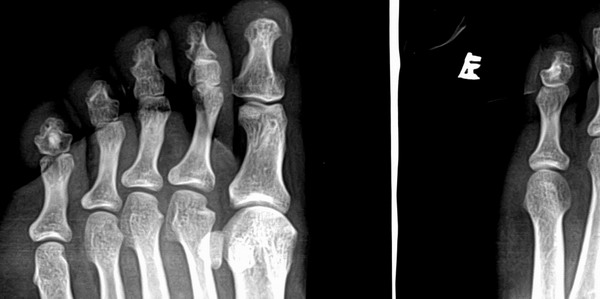

以下是引用浮华在2007-5-22 18:39:00的发言:[br]小趾中节趾骨高密度影,边界清,无明显骨质破坏--骨岛?

小趾中节趾骨高密度影,边界清,无明显骨质破坏--骨岛?

骨岛,姆趾近节关节下有个小囊装影。

应该是骨岛吧

骨岛

小趾近趾节远端透亮纹是怎么回事啊,重迭就这么巧吗?